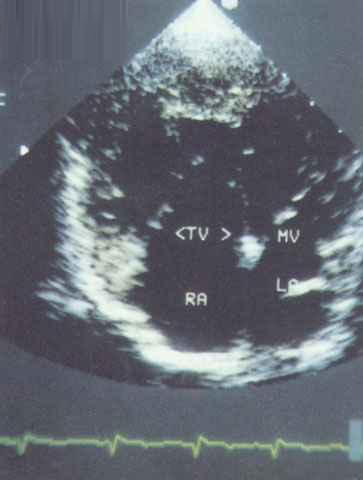

照片名称:室间隔缺损2

照片名称:单心室核01

照片名称:先天性心脏病